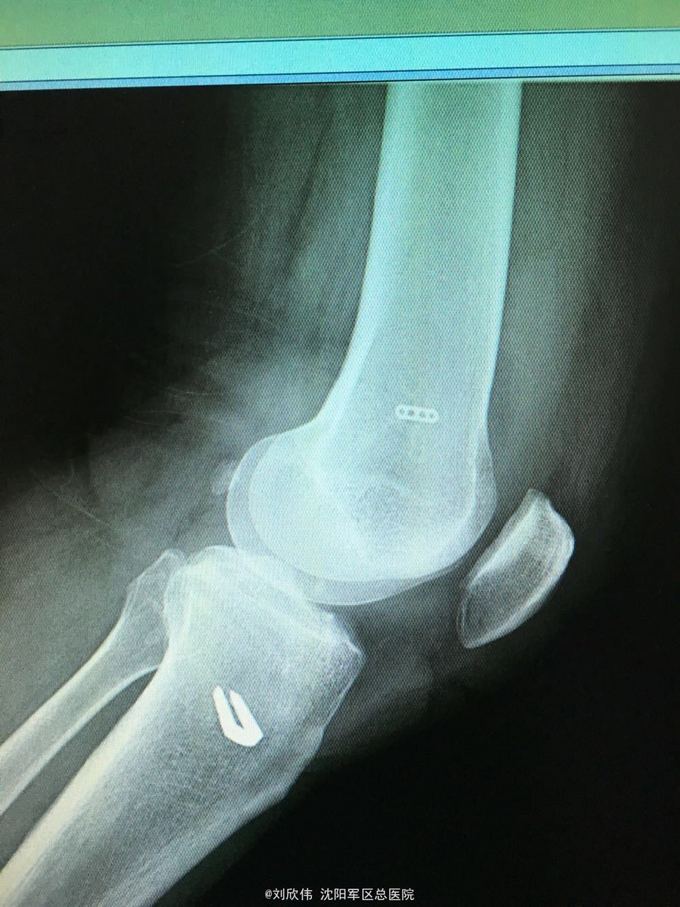

男性,44岁,摔伤所致,左膝。诊断如题

前抽屉,lachman,轴移阳性,外侧应力试验因疼痛无法进行

诊断如题,关节镜解决acl,mcl给予支具保守治疗

这个病例值得讨论的有2点,其一,mcl即内侧副韧带的处理通常可以保守治疗,二期不稳后再行手术治疗。第二,前叉胫骨侧隧道内口的位置,一个原则,宁内勿外。